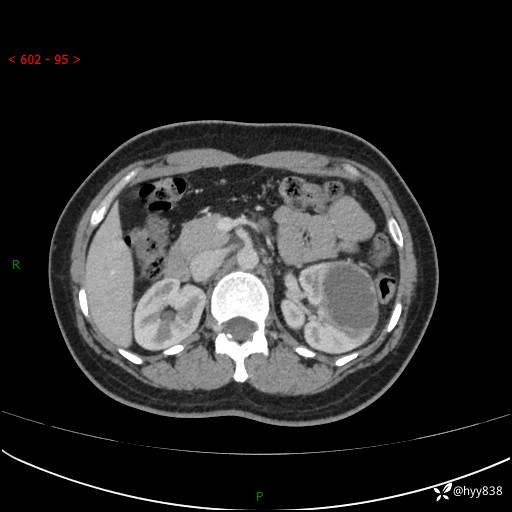

现病史:患者于1周前因左侧腰腹部间断胀痛不适,无恶心呕吐,无明显肉眼血尿,无畏寒发热,无尿频尿急,起病初,患者来我院就诊,查CT提示左肾低密度影,外周血提示:白细胞11.25*10^9/L.行抗感染治疗后未见明显好转,06-18泌尿系增强CT提示左肾类圆形低密度占位(脓肿?肿瘤?),大小:4.0*3.2cm,为求进一步治疗,门诊以“左肾占位”收住我科。 起病以来,患者精神佳,饮食、睡眠良好,大小便正常,体力体重无明显变化。

双肾CT平扫+增强